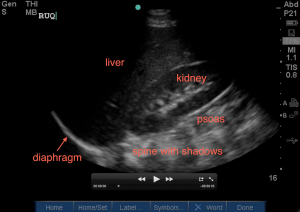

Assess that your probe is in the correct location by seeing (from top of screen to bottom): the liver on your screen and slowly angling it posteriorly to get the kidney also on your screen which is right above the psoas and then spine (with it’s shadow). If you do not see the liver, you may be too high or too low – slide down or up a rib space to get yourself oriented to the correct region with the depth usually being at 16cm.